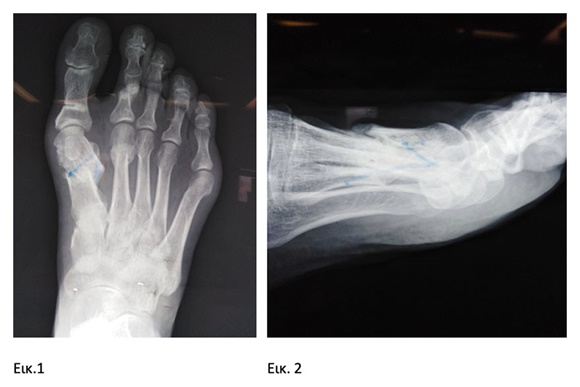

Προεγχειρητικά, φαίνεται η μεγάλη απόκλιση σε ραιβότητα του 1ου μετατάρσιου με μεγάλη βράχυνση του μηκους του (εικ 1), καθώς και η ραχιαία μετατόπισή του (εικ 2). Το αποτέλεσμα είναι να προκαλείται μεγάλη «πτώση» μεταταρσίων, με μόνιμο πόνο και αδυναμία βάδισης.